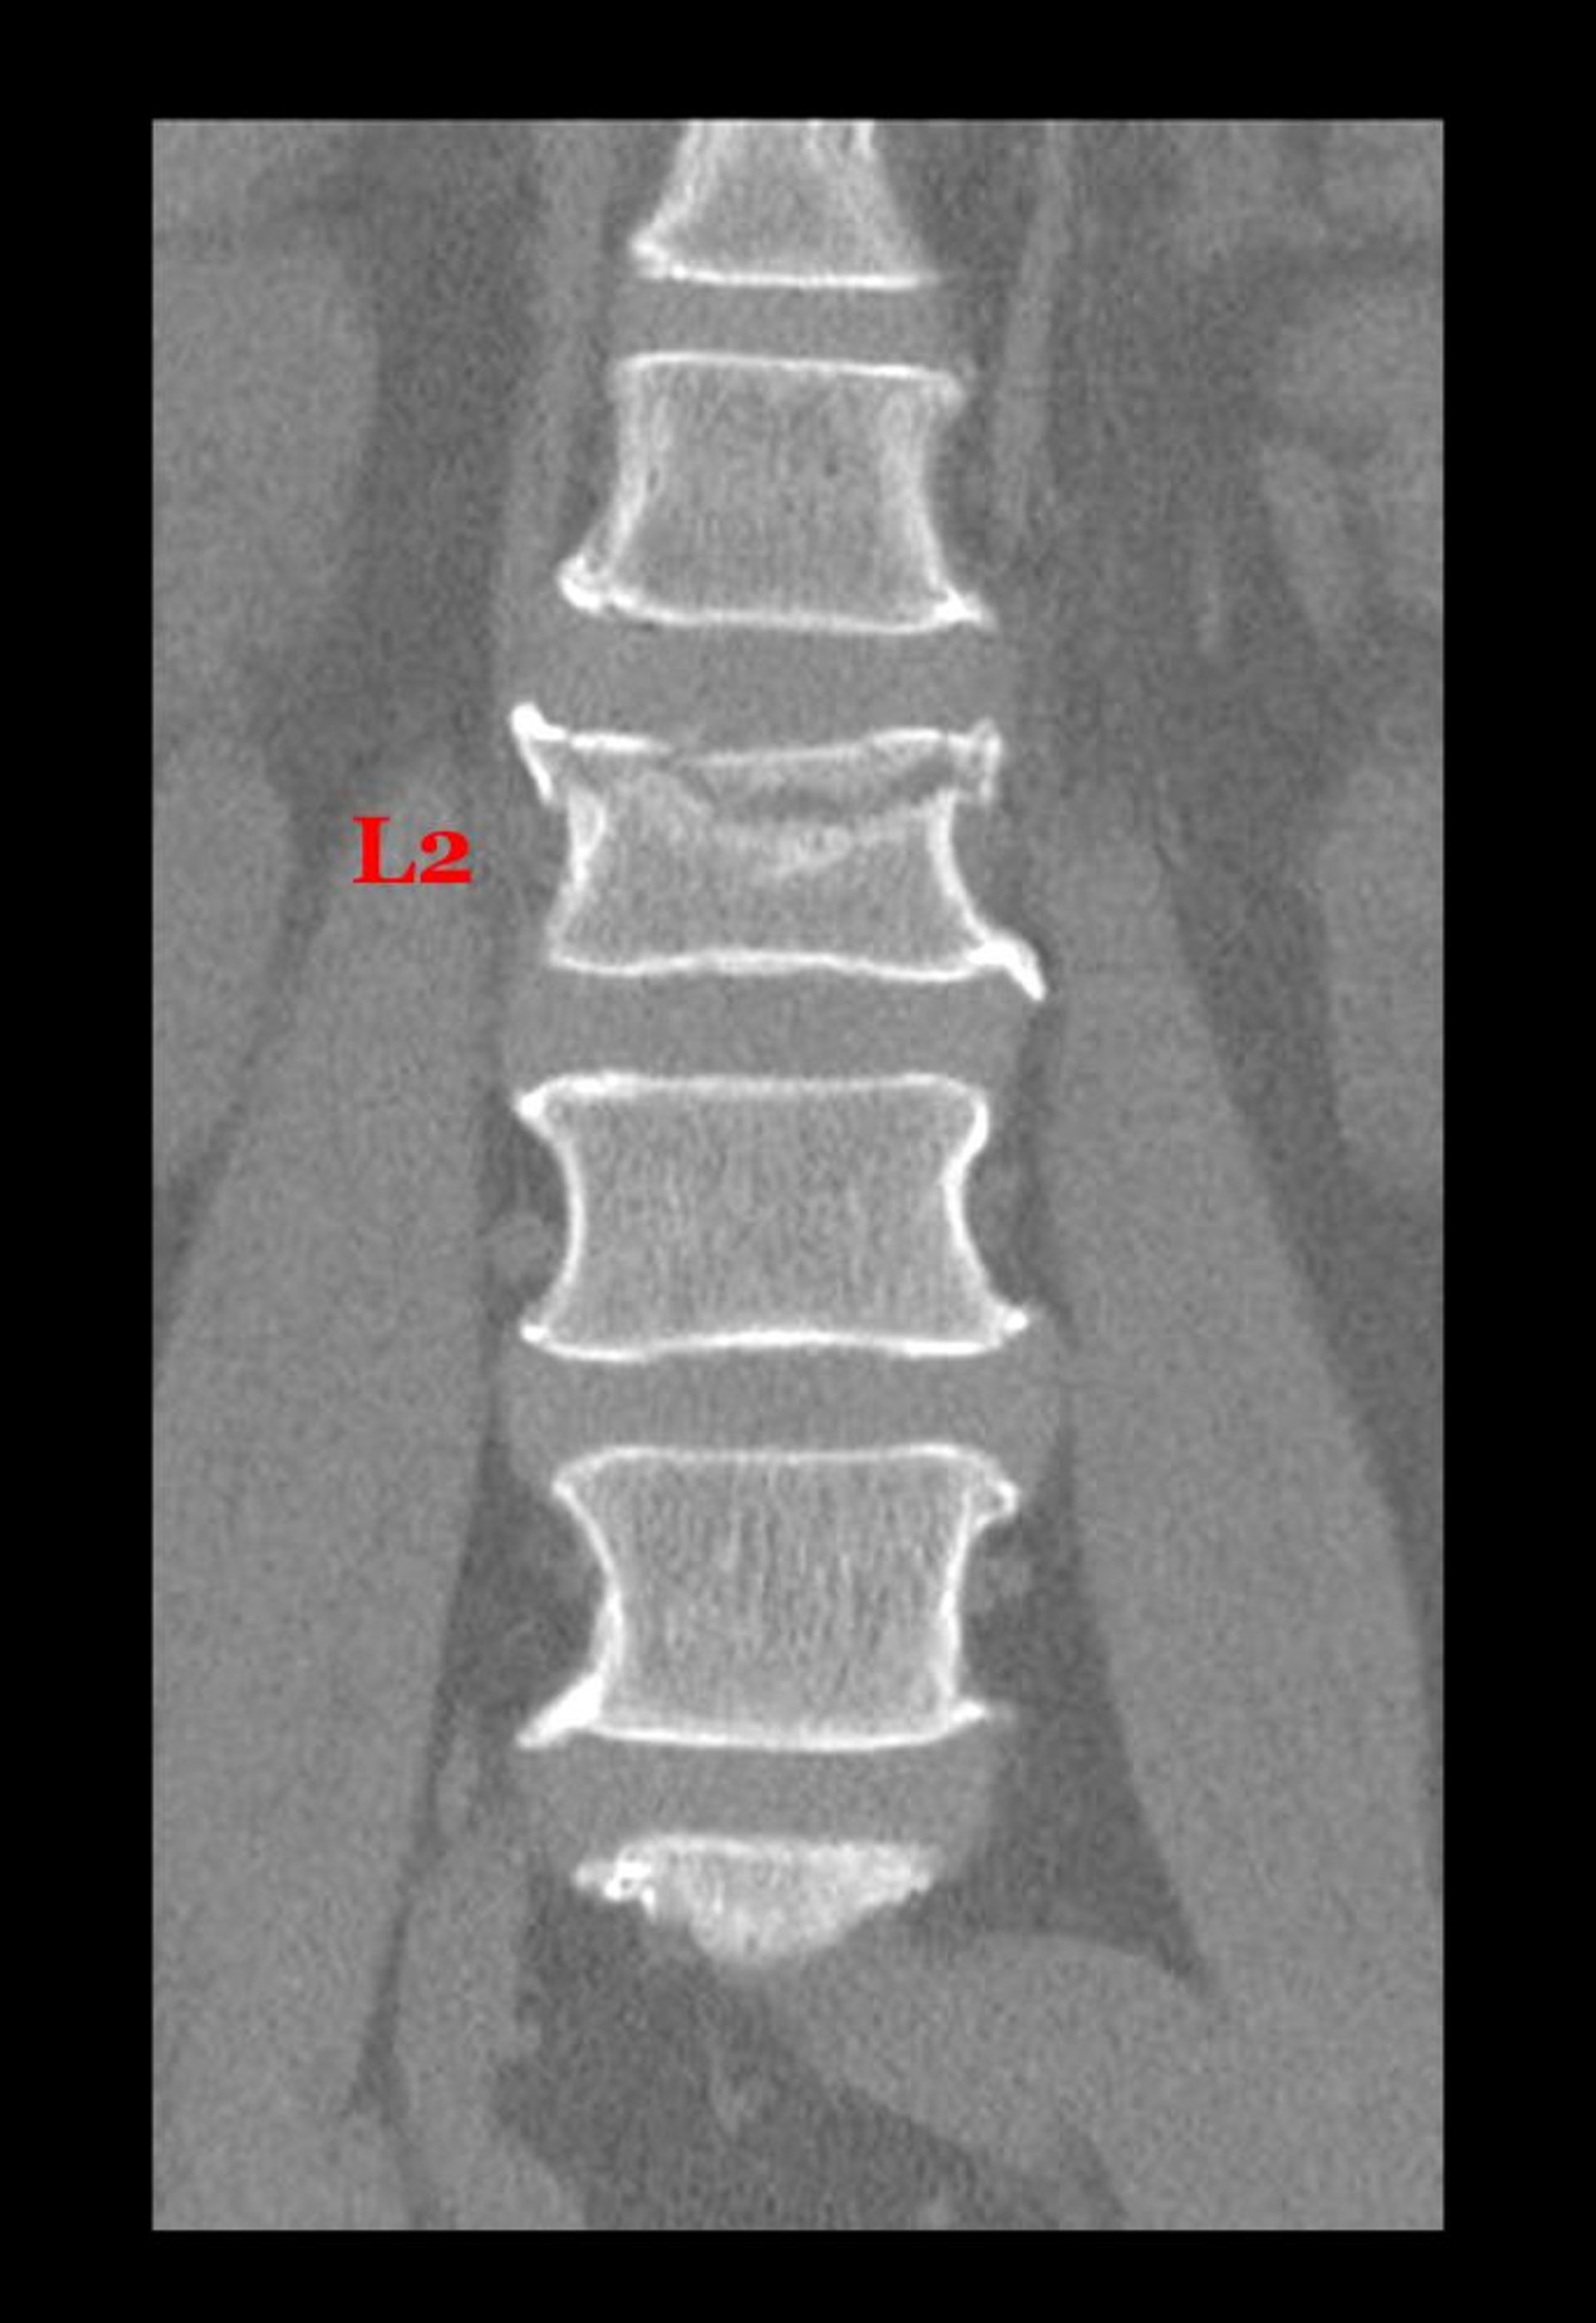

Fracture par compression (tassement) d'une vertèbre lombaire

Cette vue coronale (frontale) d'une TDM montre une fracture de la face supérieure du corps de la 2e vertèbre lombaire.